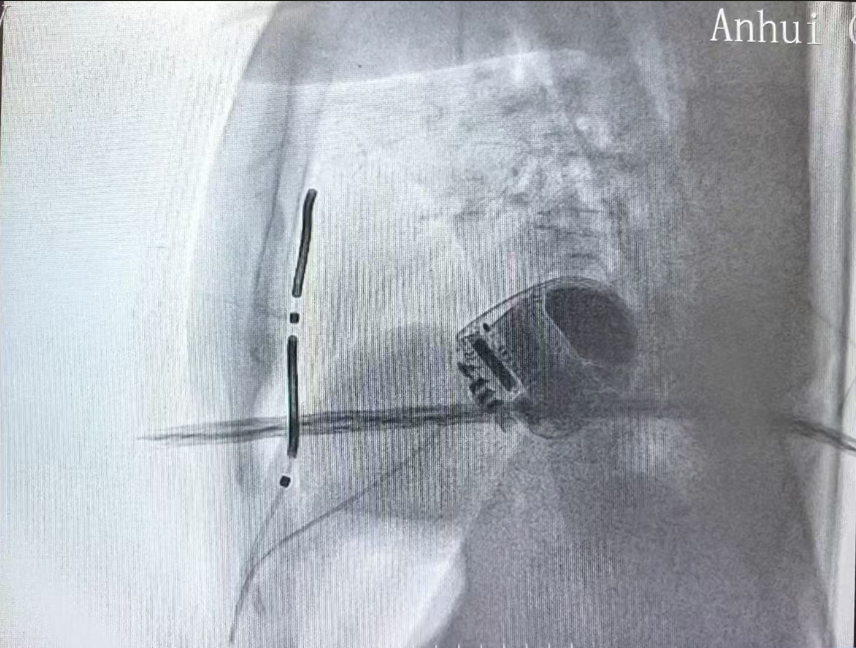

本例患者为59岁女性,扩张性心肌病病史多年,入院检查心脏超声EF25%,并且反复发作持续性室性心动过速,具有心源性猝死二级预防的适应证。在与患者及其家属充分沟通后决定植入EV-ICD血管外除颤器。术前乔青教授团队通过胸部CT仔细评估患者解剖结构,规划电极植入路径,与心外科专家、麻醉医师共同讨论手术操作细节,对术中可能遇到的问题进行了充分的讨论和准备,制定了完善的手术预案。11月11日下午植入EV-ICD,手术过程顺利,胸骨下电极稳定,电学参数正常,除颤测试通过。患者麻醉苏醒后即转回普通病房,状态良好。

Aurora EV-ICD 结合了现有经静脉和皮下ICD系统的优势,既不需要将电极植入心脏和血管内,同时实现了完整的除颤复律和抗心动过速起搏(ATP)治疗功能,装置体积小,预估使用寿命长达11.7年,为患者减少了未来设备更换的次数和经济负担。同时兼容1.5T 和3.0T MRI 全身磁共振扫描,术后更加美观舒适,不影响患者日常生活,是室性心律失常治疗及心脏性猝死防治领域的又一大技术突破。